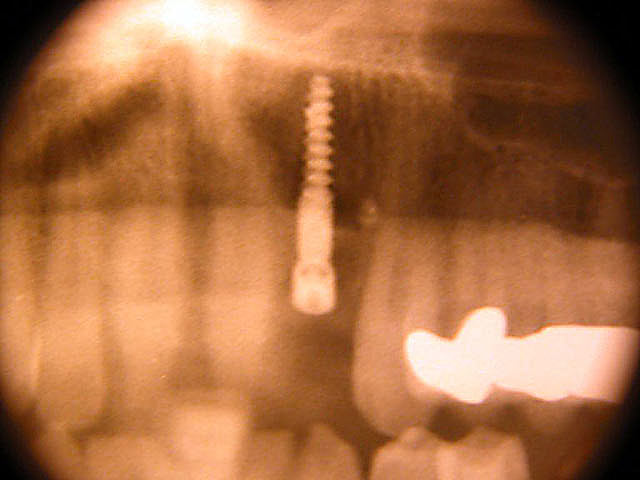

Frontzahn-Implantation: